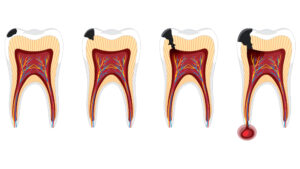

A inflamação no ápice do dente, como é chamada a ponta da raiz, e na região em volta dele tem como causa principal a cárie. Quando a cárie não é tratada, as bactérias chegam ao canal radicular do dente e o atravessam até o ápice, causando a periodontite apical. Essa condição leva à perda óssea na região.

Se não for tratada, a infecção pode levar à perda do dente. Além disso, existe uma relação bidirecional entre a periodontite apical e alterações sistêmicas do paciente. Diabetes, síndrome metabólica, arteriosclerose e doenças renais, entre outras, podem piorar o quadro da periodontite apical. Ao mesmo tempo, a infecção no ápice pode piorar quadros dessas doenças.

“É uma condição que o paciente pode nem saber que tem devido ao seu caráter crônico, mas que pode evoluir, levando à destruição óssea e mobilidade do dente. Além disso, em situações específicas, como uma queda de imunidade, pode tornar-se aguda, então, o paciente passa a sentir dor, forma-se pus no local, o rosto pode ficar inchado”, explica Rogério de Castilho Jacinto, professor da Faculdade de Odontologia de Araçatuba da Universidade Estadual Paulista (FOA-Unesp) apoiado pela FAPESP, que orientou o estudo.